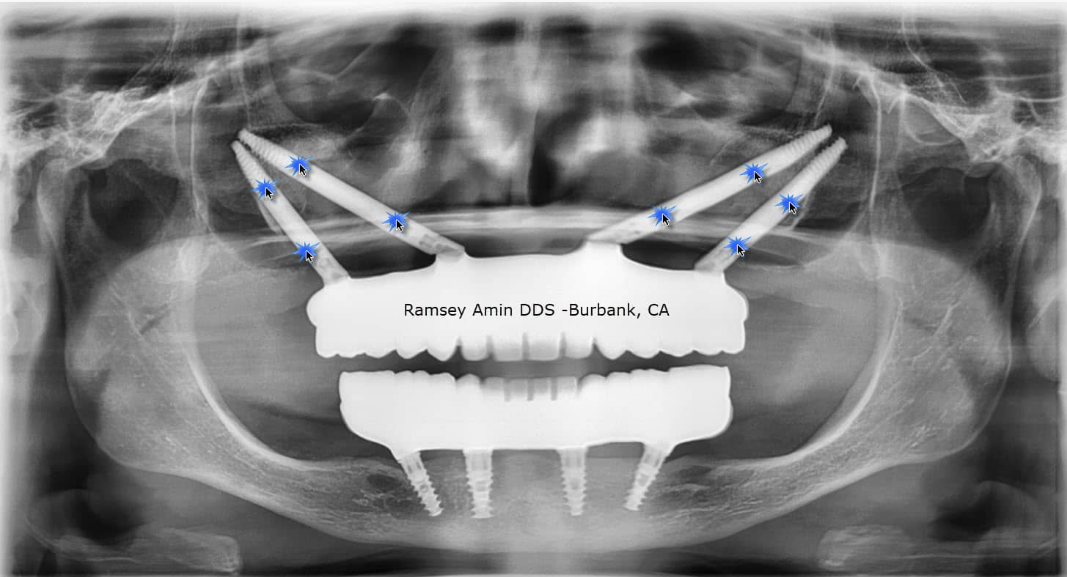

上图为四联颧骨种植体X线片。图中蓝色星标所示为颧骨种植体,每侧各植入2颗。

原作者在美国(及部分欧洲国家)开展颧骨/鼻骨/翼突种植技术培训时,始终强调需全面评估所有可选方案后再决定是否采用四联颧骨种植。值得庆幸的是,多数患者仅需常规种植体即可完成治疗,无需这些特殊植入方案。